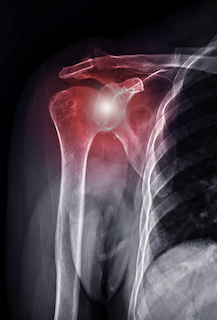

画像評価も重要な役割を果たします。X線検査により骨形態を確認し、超音波やMRIによってローテーターカフや関節唇などの軟部組織の状態を評価することで、病態の把握がより明確になります(Bolia et al., 2021)。